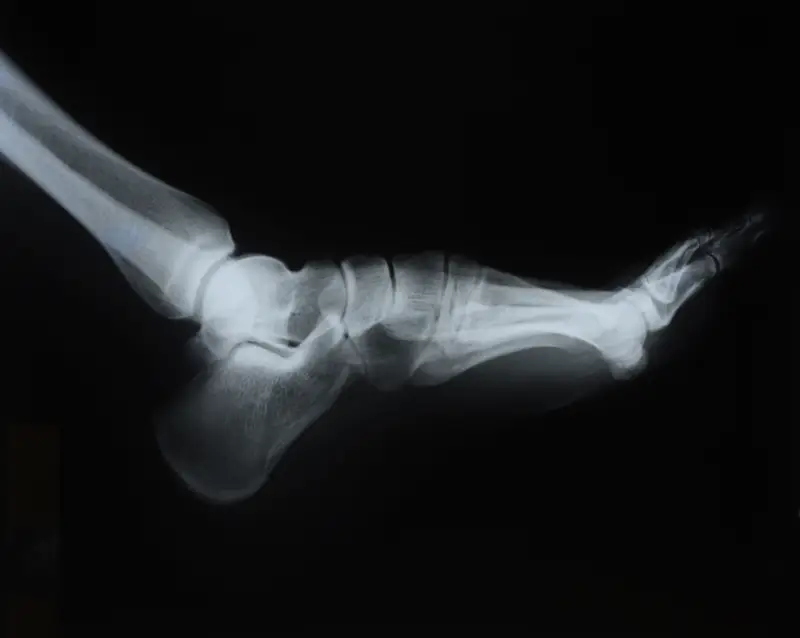

Neuropathy is damage or dysfunction of one or more nerves that typically results in numbness, tingling, muscle weakness and pain in the affected area, often starting with your feet. Over time increased numbness can lead to foot injury that goes undetected. People with lower leg and foot neuropathy should be monitored by a podiatrist to help educate on how to prevent injuries from occurring.

If you suspect a foot or ankle fracture or have any concerns about your lower extremities, we encourage you to schedule an appointment at Northern Ankle Foot Associates. Dr. Joseph is here to provide compassionate care and guide you toward a healthier, pain-free future.